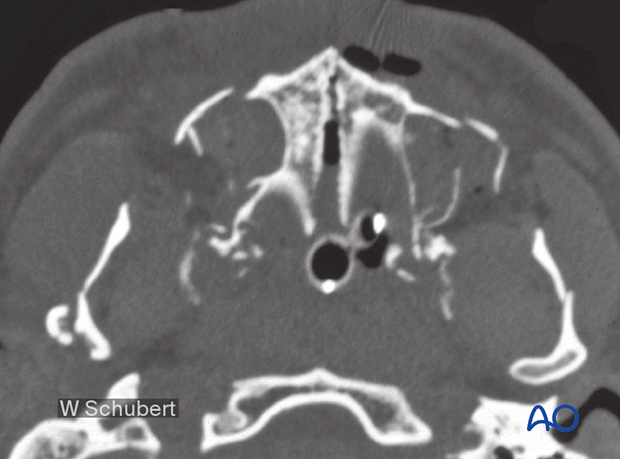

Preoperative axial CT scan.

This CT shows significant splaying of the palate in the midline. It also shows a Le Fort I fracture and significant mandibular fractures.